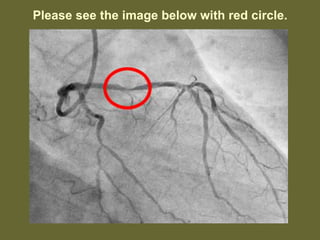

Please see the below image after the procedure.

Once they identifiedthe major block, they have done immediately a procedure called angioplasty along with two Stints, meaning they will insert an foreign body into the heart arteries and open the clocked area of the arteries.